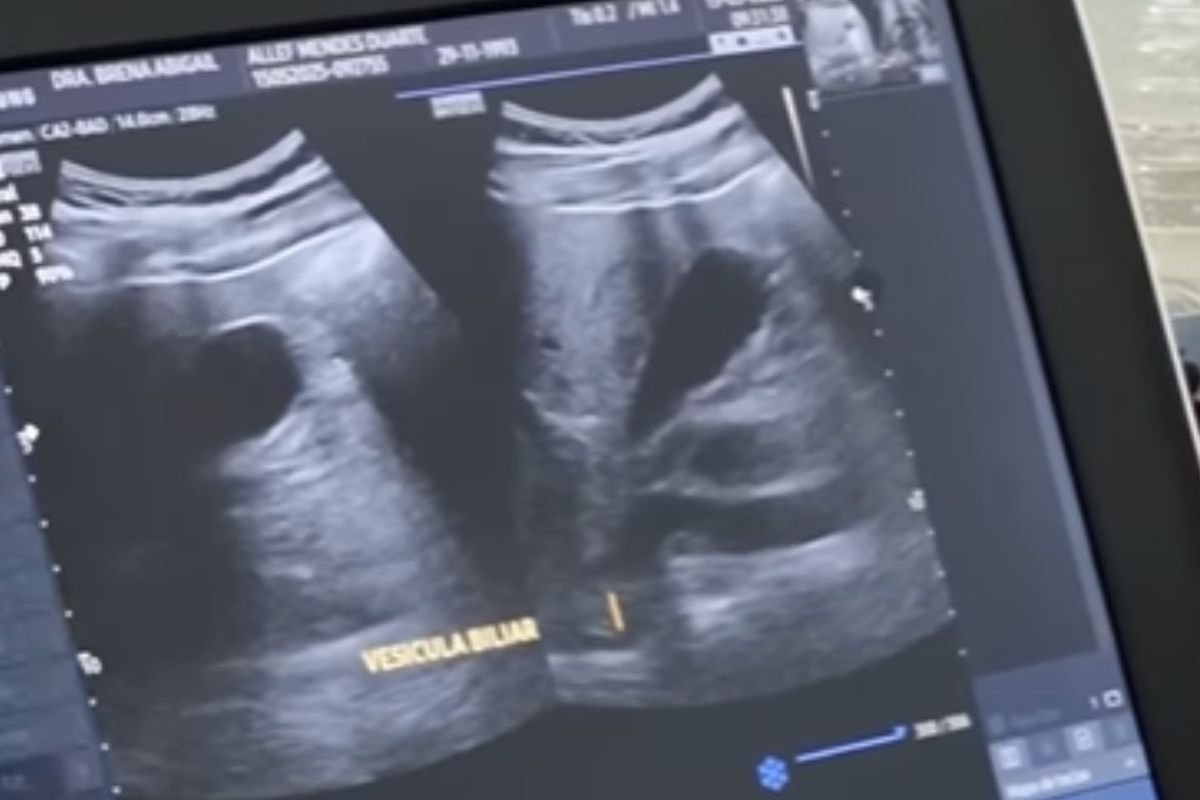

A Prefeitura de Pedro Avelino segue ampliando o acesso à saúde por meio da oferta de exames de ultrassonografia tanto na Zona Urbana quanto nas comunidades rurais. A iniciativa tem beneficiado dezenas de moradores que antes precisavam se deslocar até o centro da cidade para realizar esse tipo de atendimento.

A ação integra o conjunto de esforços da administração municipal para descentralizar os serviços de saúde e garantir mais comodidade à população. Além disso, a prefeitura tem investido em profissionais qualificados e equipamentos modernos, assegurando um atendimento eficaz e humanizado.

Com a realização das ultrassonografias nas próprias comunidades, os pacientes conseguem realizar os exames com mais rapidez e conforto. Isso também reduz o número de deslocamentos, desafoga o sistema de transporte público e contribui para diagnósticos mais ágeis.